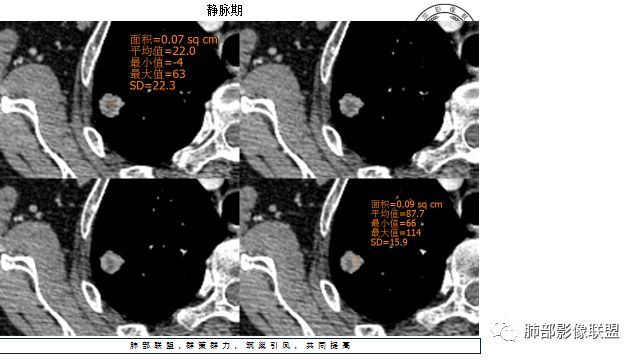

4.增强扫描成明显环形强化,中央液化坏死,内壁清楚且较为规整。

分析:

1.肺鳞癌是容易坏死,但如此小的结节出现影像明显可见的坏死区,且内壁如此清楚规整,我们临床实践中肿瘤非常少见,重要的事情说三遍!!!

好发于肺尖或尖后段胸膜下的密度不均的结节什么病最常见?结核!

小病灶常常出现空洞的什么病最常见?结核!

空洞内外壁都很清楚的什么病最常见?结核!

周围伴随小结节及条索影的什么病最常见?结核!